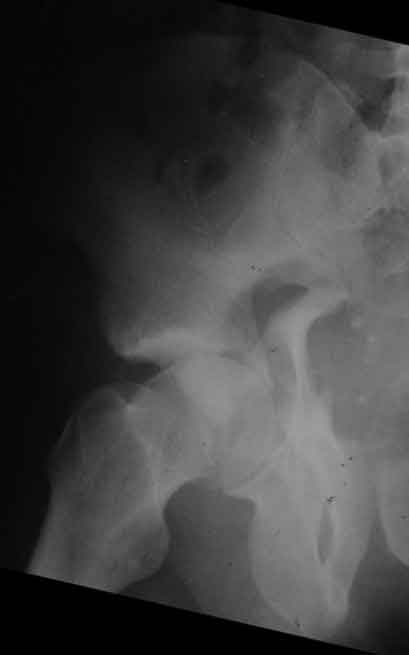

Досылаю рентгенограмму

> Досылаю рентгенограмму

Бессмысленно заниматься лечением повреждений вертлужной впадины по такой рентгенограммам, попытайтесь вправить вывих и отправить в лечебное учреждение, где занимаются лечением подобных повреждений.

Поверьте, ни в коем разе не хочу Вас обидеть, но если нет возможности сделать качественные рентгенограммы в нескольких проекциях, то грамотное лечение таких повреждений практически невозможно.